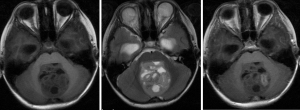

Magnetic resonance imaging (MRI) is formed by reconstructing the signal generated by the resonance of hydrogen nuclei in a magnetic field. It is a conventional non-invasive technique for evaluating MB. There are multiple parametric images in MRI, including T1 weighted image (T1WI), T2 weighted image (T2WI), diffusion weighted image (DWI), water suppression image (FLAIR) and so on. The signal performance of the same tissue on different weighted images is different, which results in a variety of different MRI images for the same patient. We analyze and integrate the patient’s multi-parameter images to obtain tumor information non-invasively. However, it is very difficult to judge the expression of Ki-67 index directly on the MRI images of MB patients, especially the result of diagnosis.

The inclusion criteria were as follows: (I) patients with available pathology (after resection); (II) patients with preoperative MRI data (see Figures 1,2); (III) patients with proven expression of the Ki-67 index by immunohistochemistry; Ki-67 index greater than or equal to 30% is defined as high expression, and Ki-67 index less than 30% is defined as low expression (see Figures 3,4); (IV) patients aged less than 18 years. A total of 271 patients were screened, and 181 patients were excluded due to the following reasons: (I) patients lacking Ki-67 expression by immunohistochemistry (n=96); (II) patients lacking at least one of the following MRI sequences: T1-weighted images (T1W), T2-weighted images (T2W), and contrast-enhanced T1-weighted images (CE-T1W) (n=71); and (III) patients with MR images that had motion or other kinds of artifacts that may affect subsequent segmentation and analysis (n=14). Finally, 90 subjects met the requirements and were included in this study (22 cases of Ki-67 index ≤30 and 68 cases of Ki-67 index >30). Clinical information (age and sex) and tumor characteristics (location, pathological type, and molecular type) are summarized in Table 1.

MR imaging acquisition

MR images were acquired on a 3T MR imaging system (Discovery 750; GE Healthcare, Milwaukee, Wisconsin) using a standard head coil. The imaging protocol for MB included the following sequences: (I) T2W [repetition time/echo time (TR/TE) =4,245/105 ms, field of view (FOV) =24 cm × 24 cm, matrix =192×192, NEX =1.5]; (II) T1W [TR/TE/TI (inversion time) =1,725/25/780 ms, FOV =24 cm × 24 cm, matrix =320×320, NEX =1]; and (III) CE-T1W acquired 2 min after intravenous administration of contrast agents (0.1 mmol/kg). The slice thickness was 5 mm with a 1.5-mm intersection space.

In our experiment, three sequences of T1W, CE-T1W, and T2W were used as test data. Two experienced radiologists (Dr. L and Dr. P, with more than 10 years of experience) manually delineated the volume of interest (VOI) on the T2W images. To save time, we used SPM12 to register T1W and T1WC to T2W. The MRI scanning system automatically calculated the co-registration among the different sequences (Figure 5).